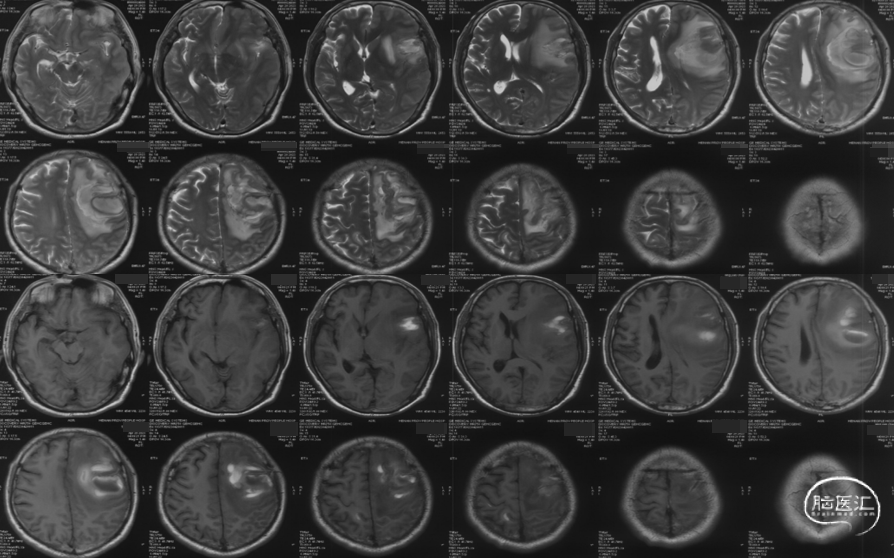

入院影像检查

CT显示左侧顶叶低密度水肿影,内见高密度血肿影;上矢状窦高密度,考虑上矢状窦血栓可能大。

MRV可见上矢状窦及右侧横窦充盈缺损。